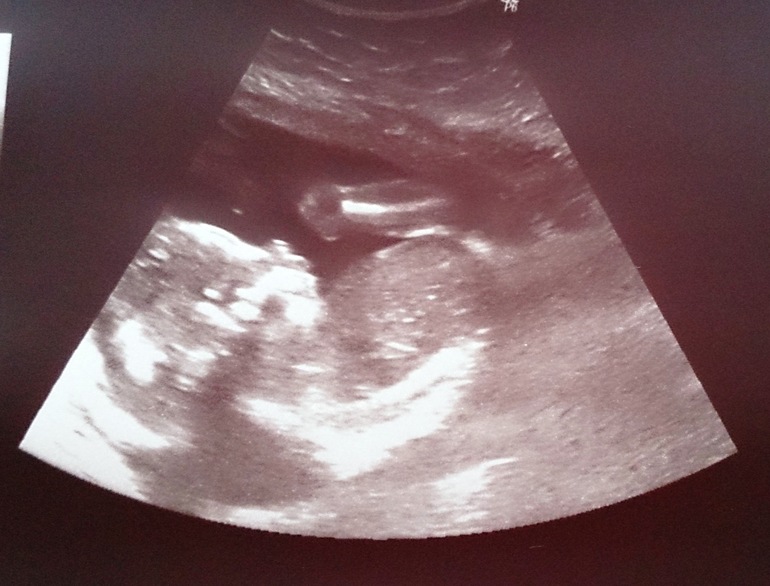

Результаты УЗИ на сроке 20,5 недель.

БПР головки - 48, лобно-затылочный размер - 64, диаметр живота - 50, длина бедренной кости - 34, длина плечевой кости - 32, примерный вес плода - 370г, ЧСС - 126.

Всё хорошо, соответсвуем срокам, как и раньше! Растём!

Ну и наконец-то рассекретили пол - это ДЕВОЧКА!!!!